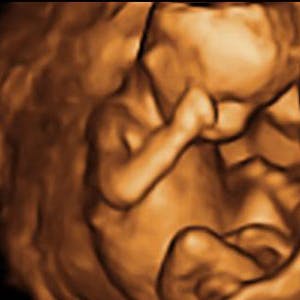

Gravid

Vi gør en dyd ud af at klæde dig godt på både før, under og efter din graviditet. Vi ved, at der kan komme mange spørgsmål til din graviditet, fødsel, amning, din babys udvikling og mange flere emner, derfor har vi samlet guides, tips & tricks samt læsernes egne fortællinger i dette gravid univers.